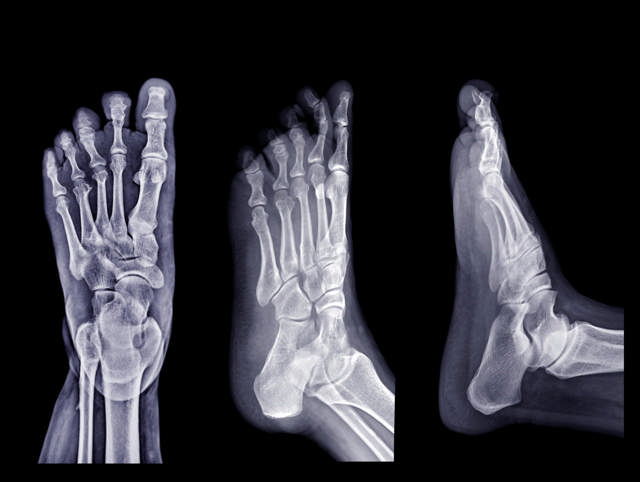

I en del tilfeller kan røntgen vise forandringer som er typiske for psoriasisartritt (iStock).